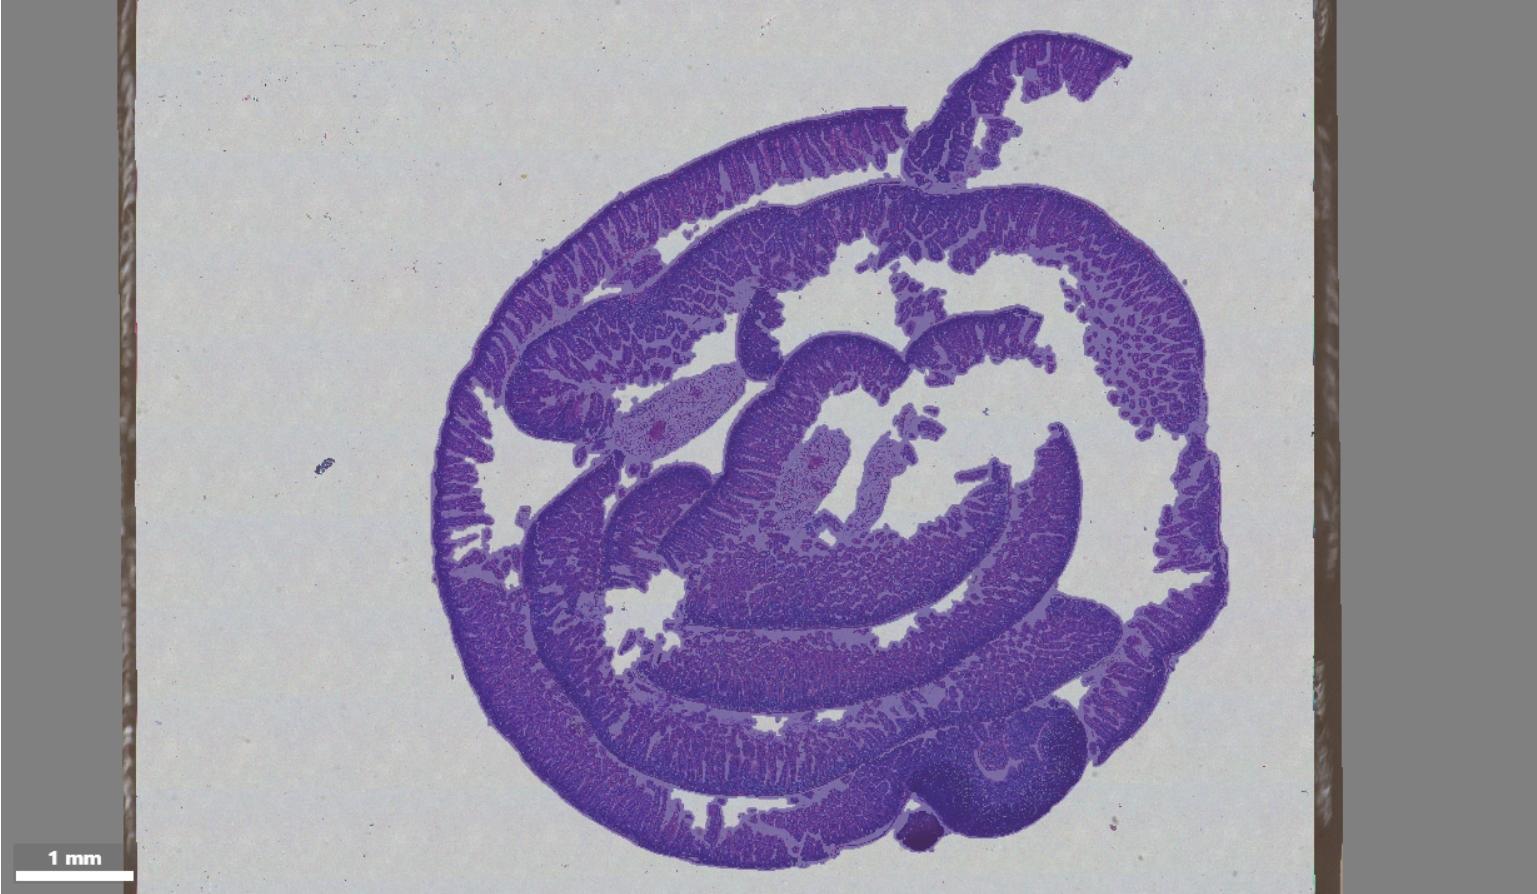

A matrix heatmap and an H&E-stained image for registration

Tissue segmentation on an H&E-stained image